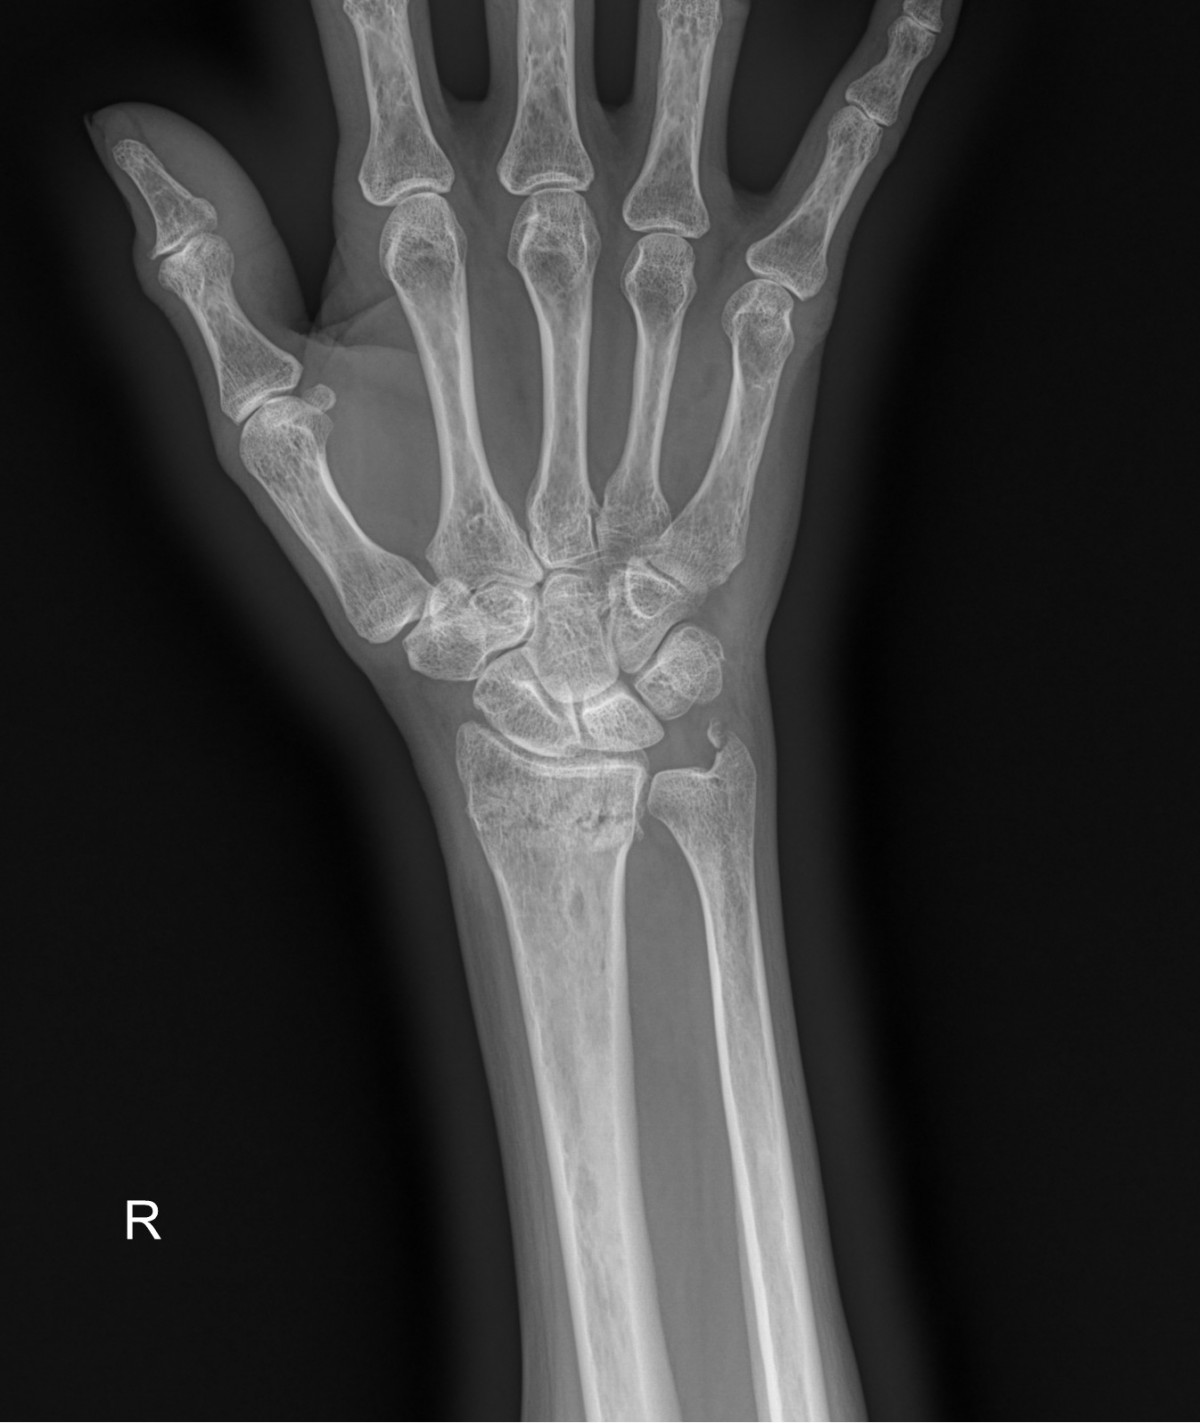

정지영원장님 손목 골절 수술 조효O 환자

dae765e4d9ac96aee867c9d6292d8784_1758008099_0498.jpg